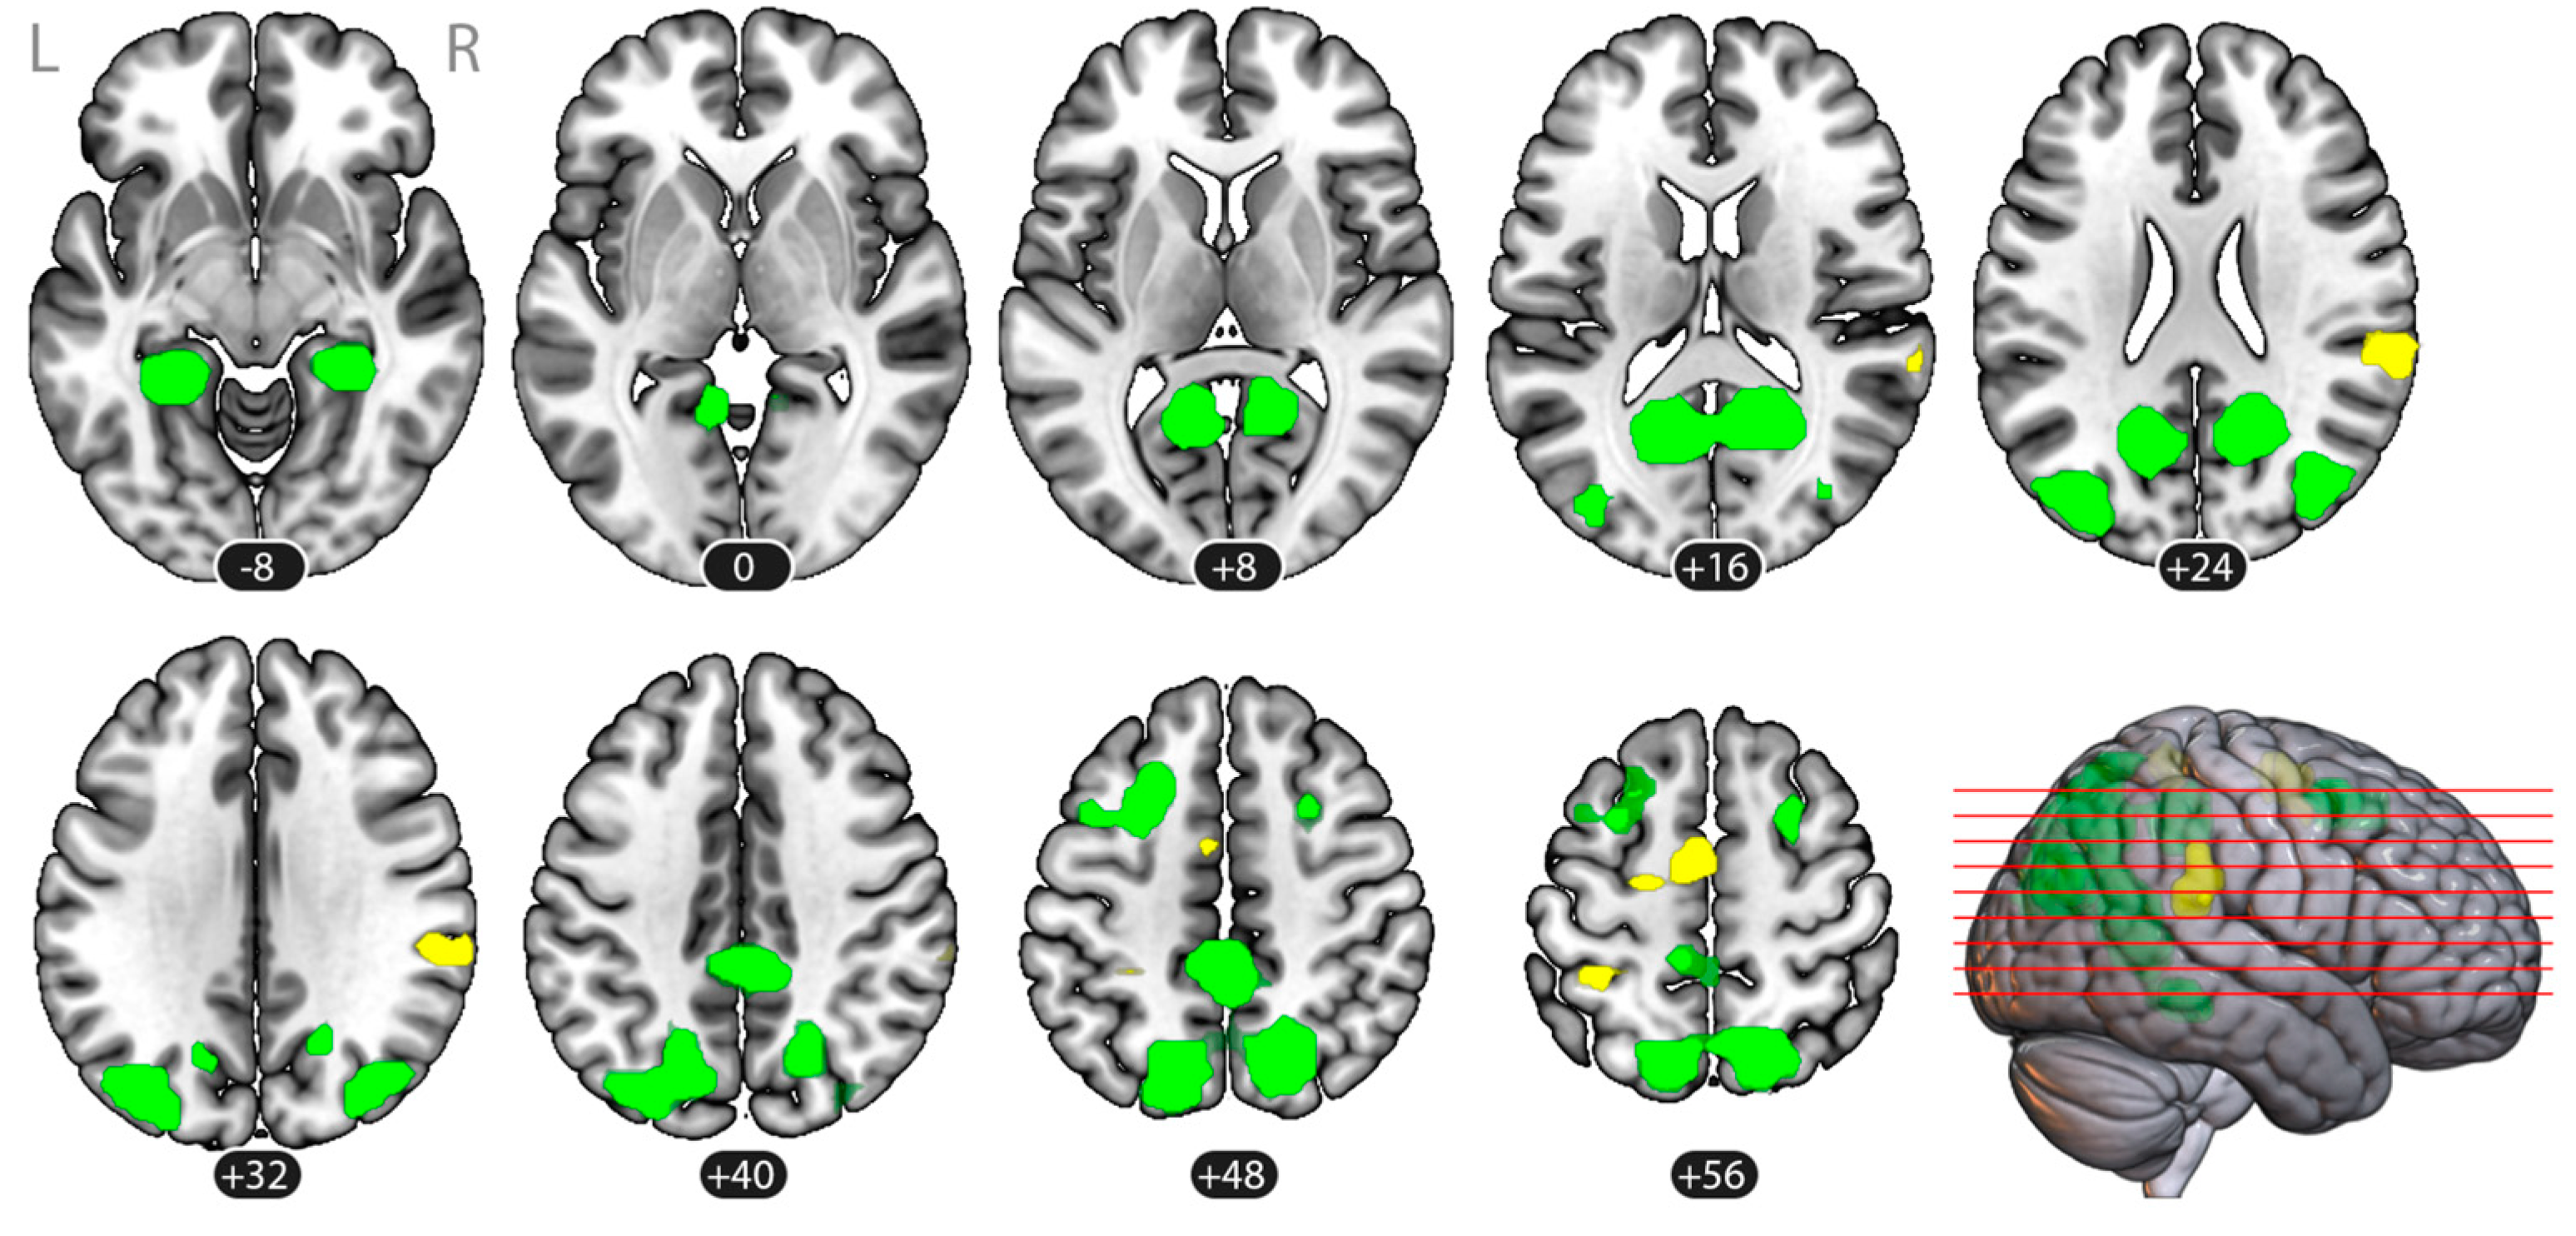

3.2. Brain Activation

| Cluster | Volume, Voxels (mm3) | pFDR | MNI Coordinates (Center of Mass) | Region Labels 1 | ||

|---|---|---|---|---|---|---|

| x | y | z | ||||

| Imagery > Rest (Baseline) | ||||||

| (1) Frontal Bilateral | 1961 (125,504) | <0.001 | −7 | 2 | 32 | Middle Frontal Gyrus (MidFG), LR Precentral Gyrus (PreCG),LR Superior Frontal Gyrus (SFG), LR Supplementary Motor Cortex (SMA), LR Thalamus, LR Putamen, LR |

| (2) Parietal Bilateral | 665 (42,560) | <0.001 | −14 | −52 | 52 | Precuneous Cortex Superior Parietal Lobule (SPL), LR Lateral Occipital Cortex, superior division (sLOC), LR Postcentral Gyrus (PostCG), L Supramarginal Gyrus, posterior division (pSMG), L |

| (3) Occipito-temporal Left | 127 (8128) | <0.001 | −42 | −68 | 19 | Lateral Occipital Cortex, superior division (sLOC), L Middle Temporal Gyrus, temporooccipital part (toMTG), L |

| (4) Occipital Right | 59 (3776) | 0.002 | 40 | −69 | 25 | Lateral Occipital Cortex, superior division (sLOC), R |

| (5) Parietal Right | 33 (2112) | 0.020 | 36 | −39 | 39 | Supramarginal Gyrus, posterior division (pSMG), R Superior Parietal Lobule (SPL), R |

| Rest (Baseline) > Imagery | ||||||

| (1) Right Operculum | 658 (28,032) | <0.001 | 48 | −17 | 8 | Central Opercular Cortex (CO), R Parietal Operculum Cortex (PO), R Insular Cortex (IC), R Middle Temporal Gyrus, posterior division (pMTG), R Superior Temporal Gyrus, posterior division (pSTG), R Heschl’s Gyrus (HG), R Planum Temporale (PT), R |

| (2) Left Operculum | 354 (42,112) | <0.001 | −49 | −23 | 7 | Central Opercular Cortex (CO), L Parietal Operculum Cortex (PO), L Insular Cortex (IC), L Middle Temporal Gyrus, posterior division (pMTG), L Superior Temporal Gyrus, posterior division (pSTG), L Heschl’s Gyrus (HG), L Planum Temporale (PT), L Planum OPerculum (PO), L |

| (3) Occipital Bilateral | 438 (22,656) | <0.001 | 5 | −79 | 14 | Lateral Occipital Cortex, superior division (sLOC), LR Lateral Occipital Cortex, inferior division (iLOC), LR Cuneal Cortex, LR Occipital Pole (OP), LR Lingual Gyrus (LG), LR |

| (4) Medial Frontal | 281 (17,984) | <0.001 | 7 | 48 | 16 | Paracingulate Gyrus (PaCiG), LR Cingulate Gyrus, anterior division (AC) Frontal Pole (FP), R Superior Frontal Gyrus (SFG), LR |

| (5) Left Angular Gyrus | 25 (1600) | 0.028 | −53 | −54 | 31 | Angular Gyrus (AG), L |

| (6) Right Angular Gyrus | 24 (1536) | 0.028 | 55 | −54 | 35 | Angular Gyrus (AG), R |

| (7) Posterior Cingulate | 36 (2304) | 0.014 | 4 | −19 | 46 | Cingulate Gyrus, posterior division (PC) Precentral Gyrus (PreCG), R |

| (8) Right Postcentral | 32 (2048) | 0.017 | 49 | −20 | 52 | Postcentral Gyrus (PostCG), R |

| (9) Left Postcentral | 24 (1536) | 0.028 | −44 | −22 | 61 | Postcentral Gyrus (PostCG), L |